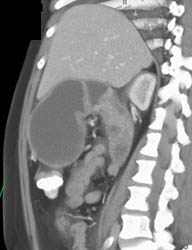

Antral Carcinoma